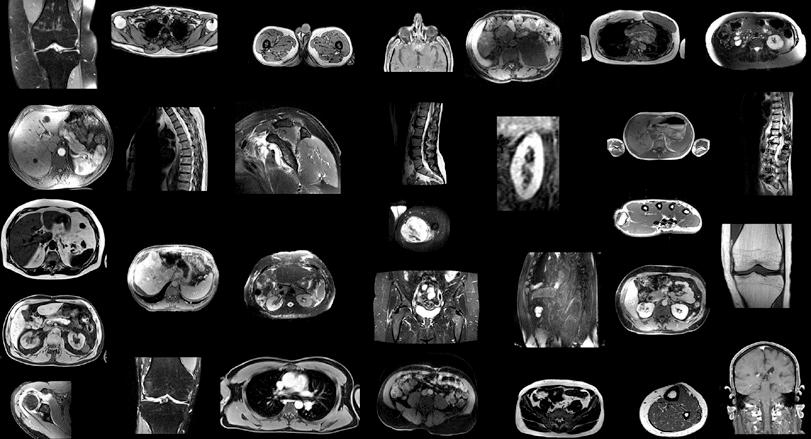

1. Ejemplos de imágenes de resonancia magnética en el conjunto de datos de entrenamiento. Dado que las imágenes se tomaron de manera aleatoria de la rutina clínica, el conjunto de datos (n = 561) contiene una amplia variedad de contrastes, patologías y tipos de imágenes diferentes.

En el estudio retrospectivo, los investigadores entrenaron TotalSegmentator MRI para proporcionar segmentaciones independientes de la secuencia de las principales estructuras anatómicas utilizando un conjunto de datos muestreados aleatoriamente de 616 exámenes de resonancia magnética y 527 de tomografía computarizada.

Figura 4. Los histogramas muestran la distribución de diferentes parámetros del conjunto de datos de entrenamiento, lo que demuestra la alta diversidad del conjunto de datos (561 exploraciones de resonancia magnética y 527 imágenes de TC). angio = angiografía, bds = ambos lados, EP = eco planar, IR = recuperación de inversión, isg = articulación sacroilíaca, GR = gradiente recordado, RM = movimiento respiratorio, SE = eco de espín.